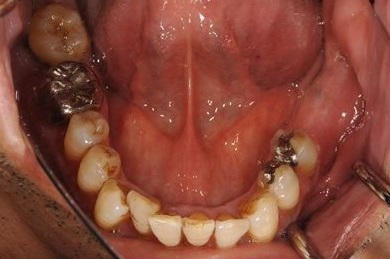

| 性別/年齢 | 男性 / 60歳 | ||||||||||||||||||||||||||||||||

| 主訴 | 右下奥歯の治療相談。(痛み・ぐらつき・物がかめない) | ||||||||||||||||||||||||||||||||

| 治療方針 | 左下奥の欠損部分をインプラント治療にて、機能的・審美的に回復を行う。 | ||||||||||||||||||||||||||||||||

| 治療内容 | インプラント2本、メタルボンドセラミッククラウン2本 | ||||||||||||||||||||||||||||||||

| 総治療費 | 680,610円 | ||||||||||||||||||||||||||||||||

| 治療期間 | 7ヶ月 |